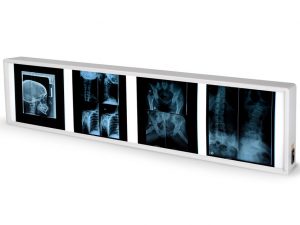

Negativoscopi, Negativoscopi linea qualitò GIMA

NEGATIVOSCOPIO TRIPLO 38 x 122 cm.

435,00 € (530,70 € IVA incl.) -

Negativoscopi, Negativoscopi linea qualitò GIMA

NEGATIVOSCOPIO QUADRUPLO 38 x 153 cm.

550,00 € (671,00 € IVA incl.) -

Negativoscopi, Negativoscopi linea qualitò GIMA

NEGATIVOSCOPIO VERTICALE 92 x 38 cm.

325,00 € (396,50 € IVA incl.) -

Negativoscopi, Negativoscopi linea qualitò GIMA

NEGATIVOSCOPIO VERTICALE 122 x 38 cm.

430,00 € (524,60 € IVA incl.) -